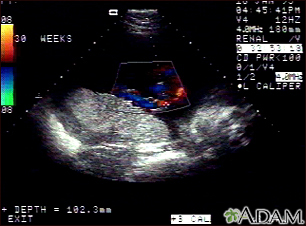

Ultrasound, color - normal umbilical cord